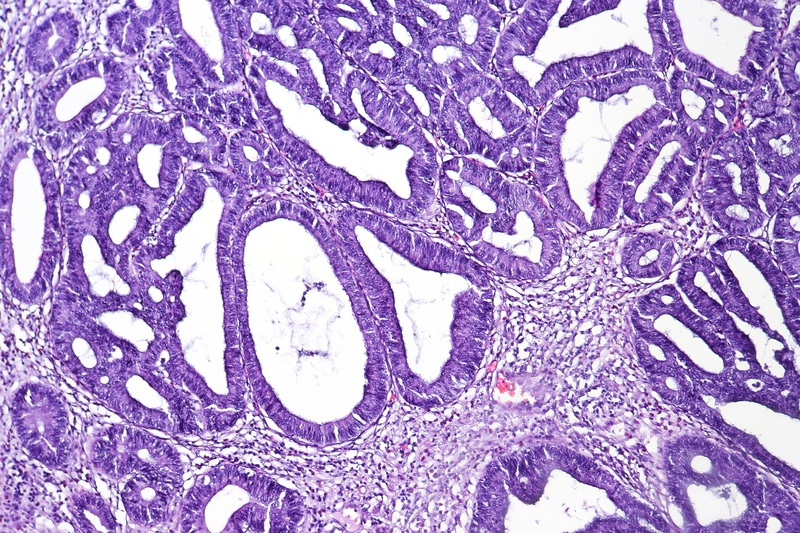

Polyp tuyến hay u tuyến là tổn thương tiền ung thư, có thể được chia thành ba loại, bao gồm u tuyến ống, u tuyến nhung mao và u tuyến ống-nhung mao, trong đó u tuyến ống là phổ biến nhất. U tuyến ống đại tràng là sự tăng trưởng tiền ung thư phát sinh từ các tế bào bao phủ bên trong đại tràng. Nó được coi là sự phát triển tiền ung thư vì theo thời gian nó có thể tiến triển thành ung thư biểu mô tuyến xâm lấn đại tràng.

Tất cả các u tuyến ống đều biểu hiện một mô hình tăng trưởng bất thường, kích thước, hình dạng và sự sắp xếp của các tế bào tăng sinh khác với các tế bào trưởng thành bình thường được gọi là nghịch sản hay loạn sản. Chứng nghịch sản này rất quan trọng vì đây là tình trạng tiền ung thư có thể trở thành ung thư theo thời gian. Khi kiểm tra u tuyến ống, các nhà nghiên cứu bệnh học phân loại chứng nghịch sản thành hai loại là chứng nghịch sản độ thấp và chứng nghịch sản độ cao.

Mức độ tăng sản không điển hình của tế bào biểu mô tuyến có ý nghĩa rất lớn trong việc đánh giá mức độ tổn thương của u tuyến và tiên lượng.